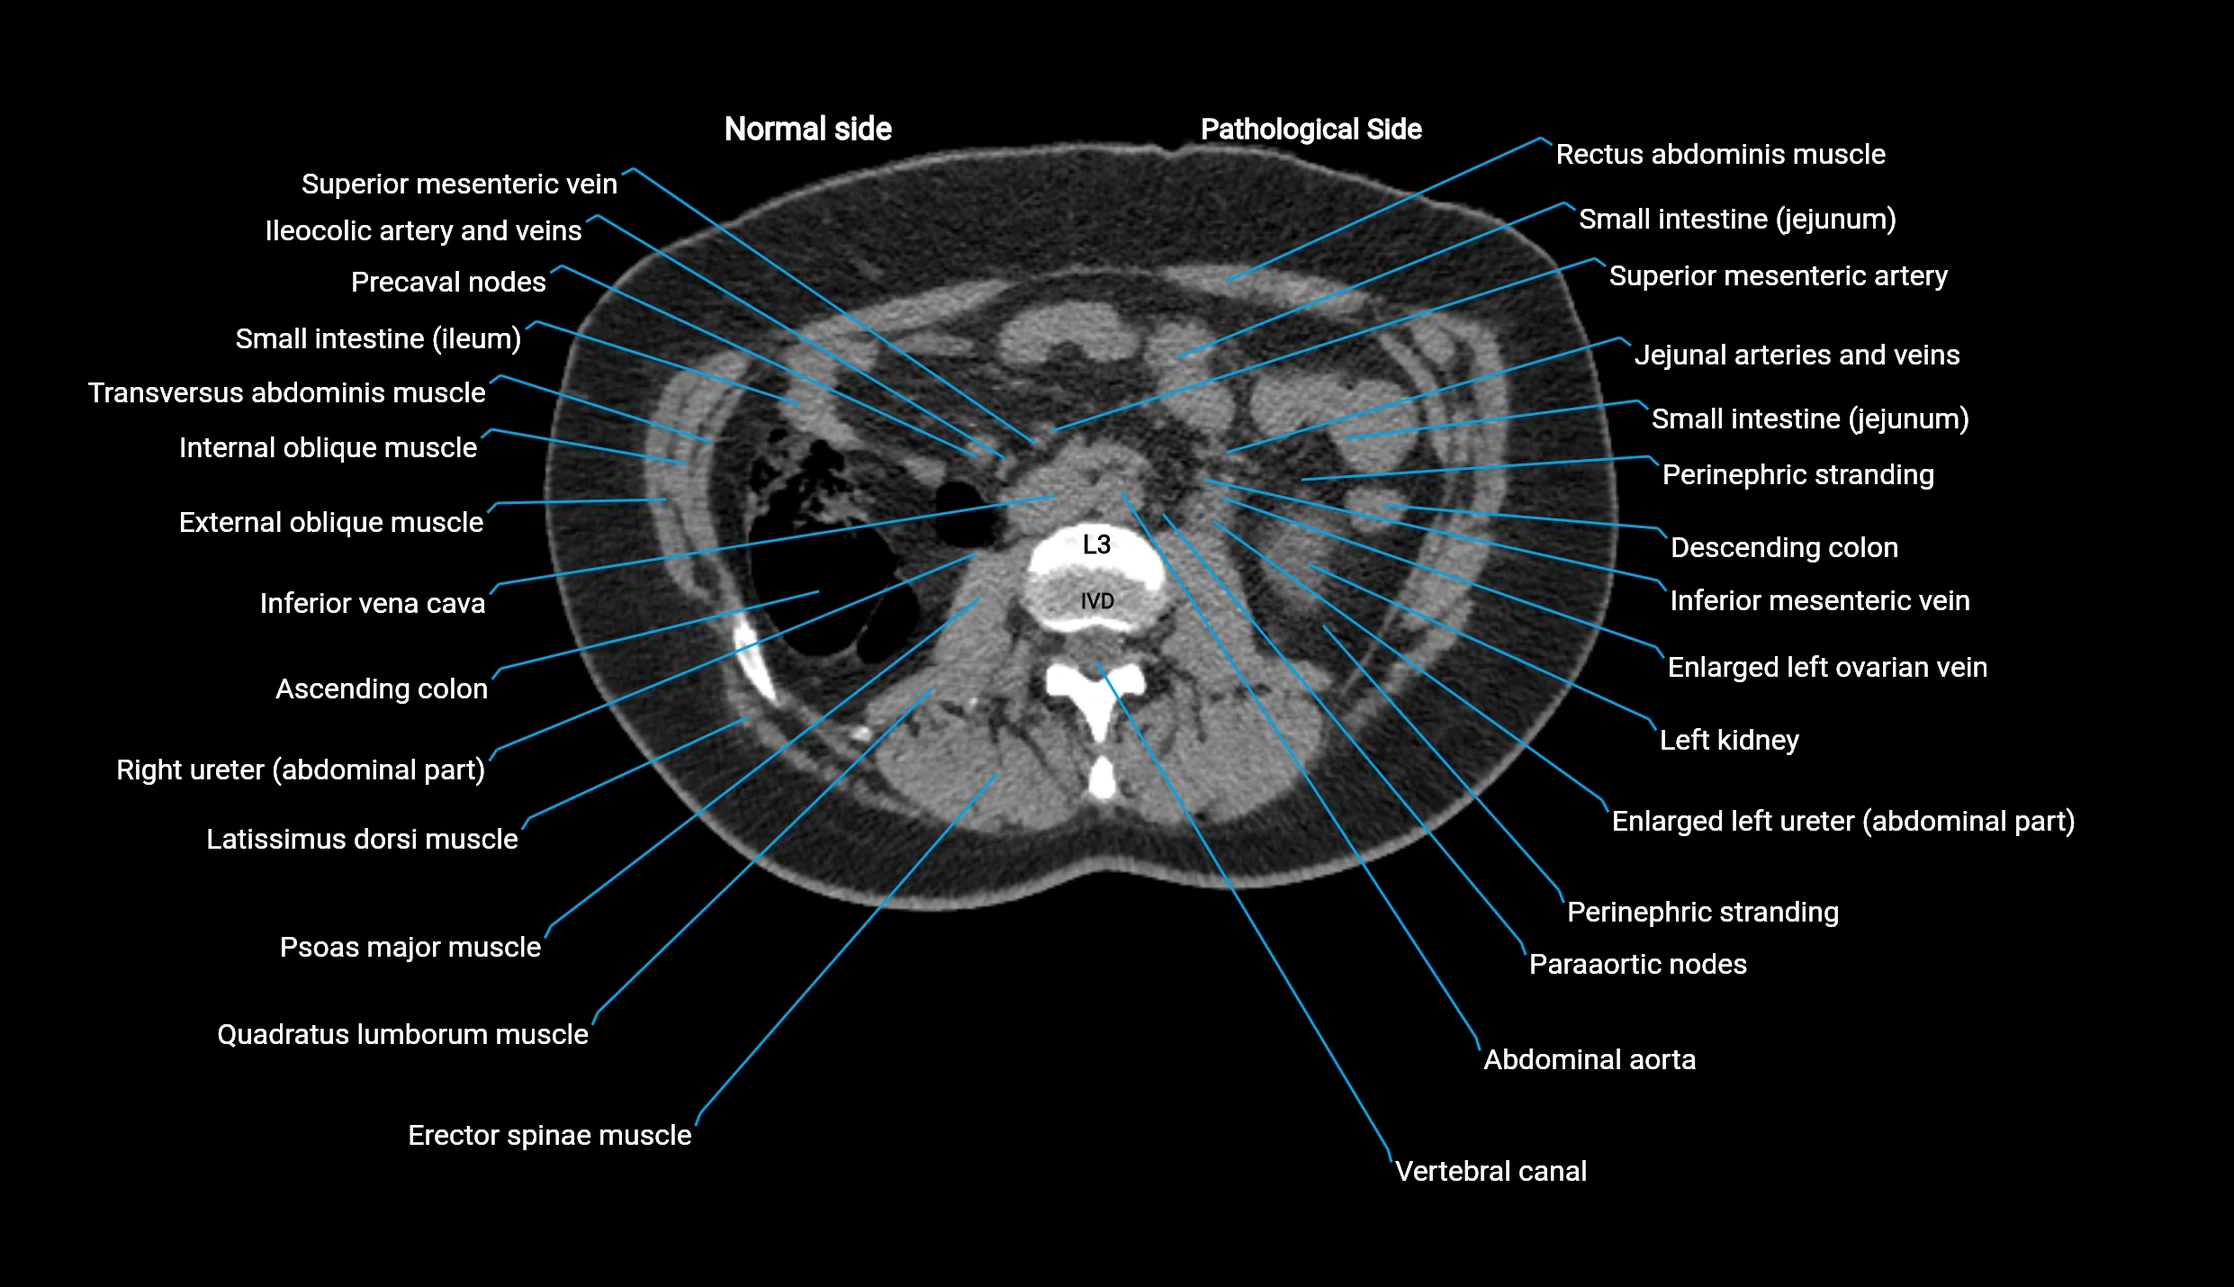

CT image

image